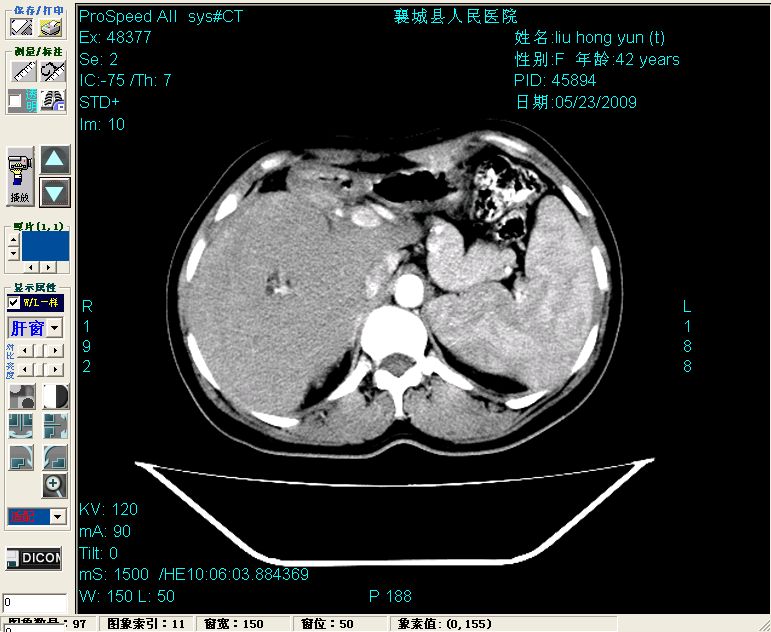

增强:

增强动脉期前述低密度区轻度早其强化,门脉期强化程度显著增高,延期扫描强化程度下降,但仍为相对高密度影

胰头部见结节状高密度影,其前方略可分辨扩强胆部管,平扫到增强始终有,但现在尚难与胃肠造影剂鉴别.